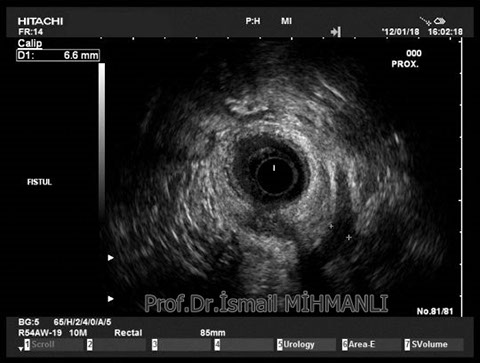

Transsfinkterik fistül

Fistüle makat kası hasarı eşlik ediyorsa endoanal US'de tespit edilir.